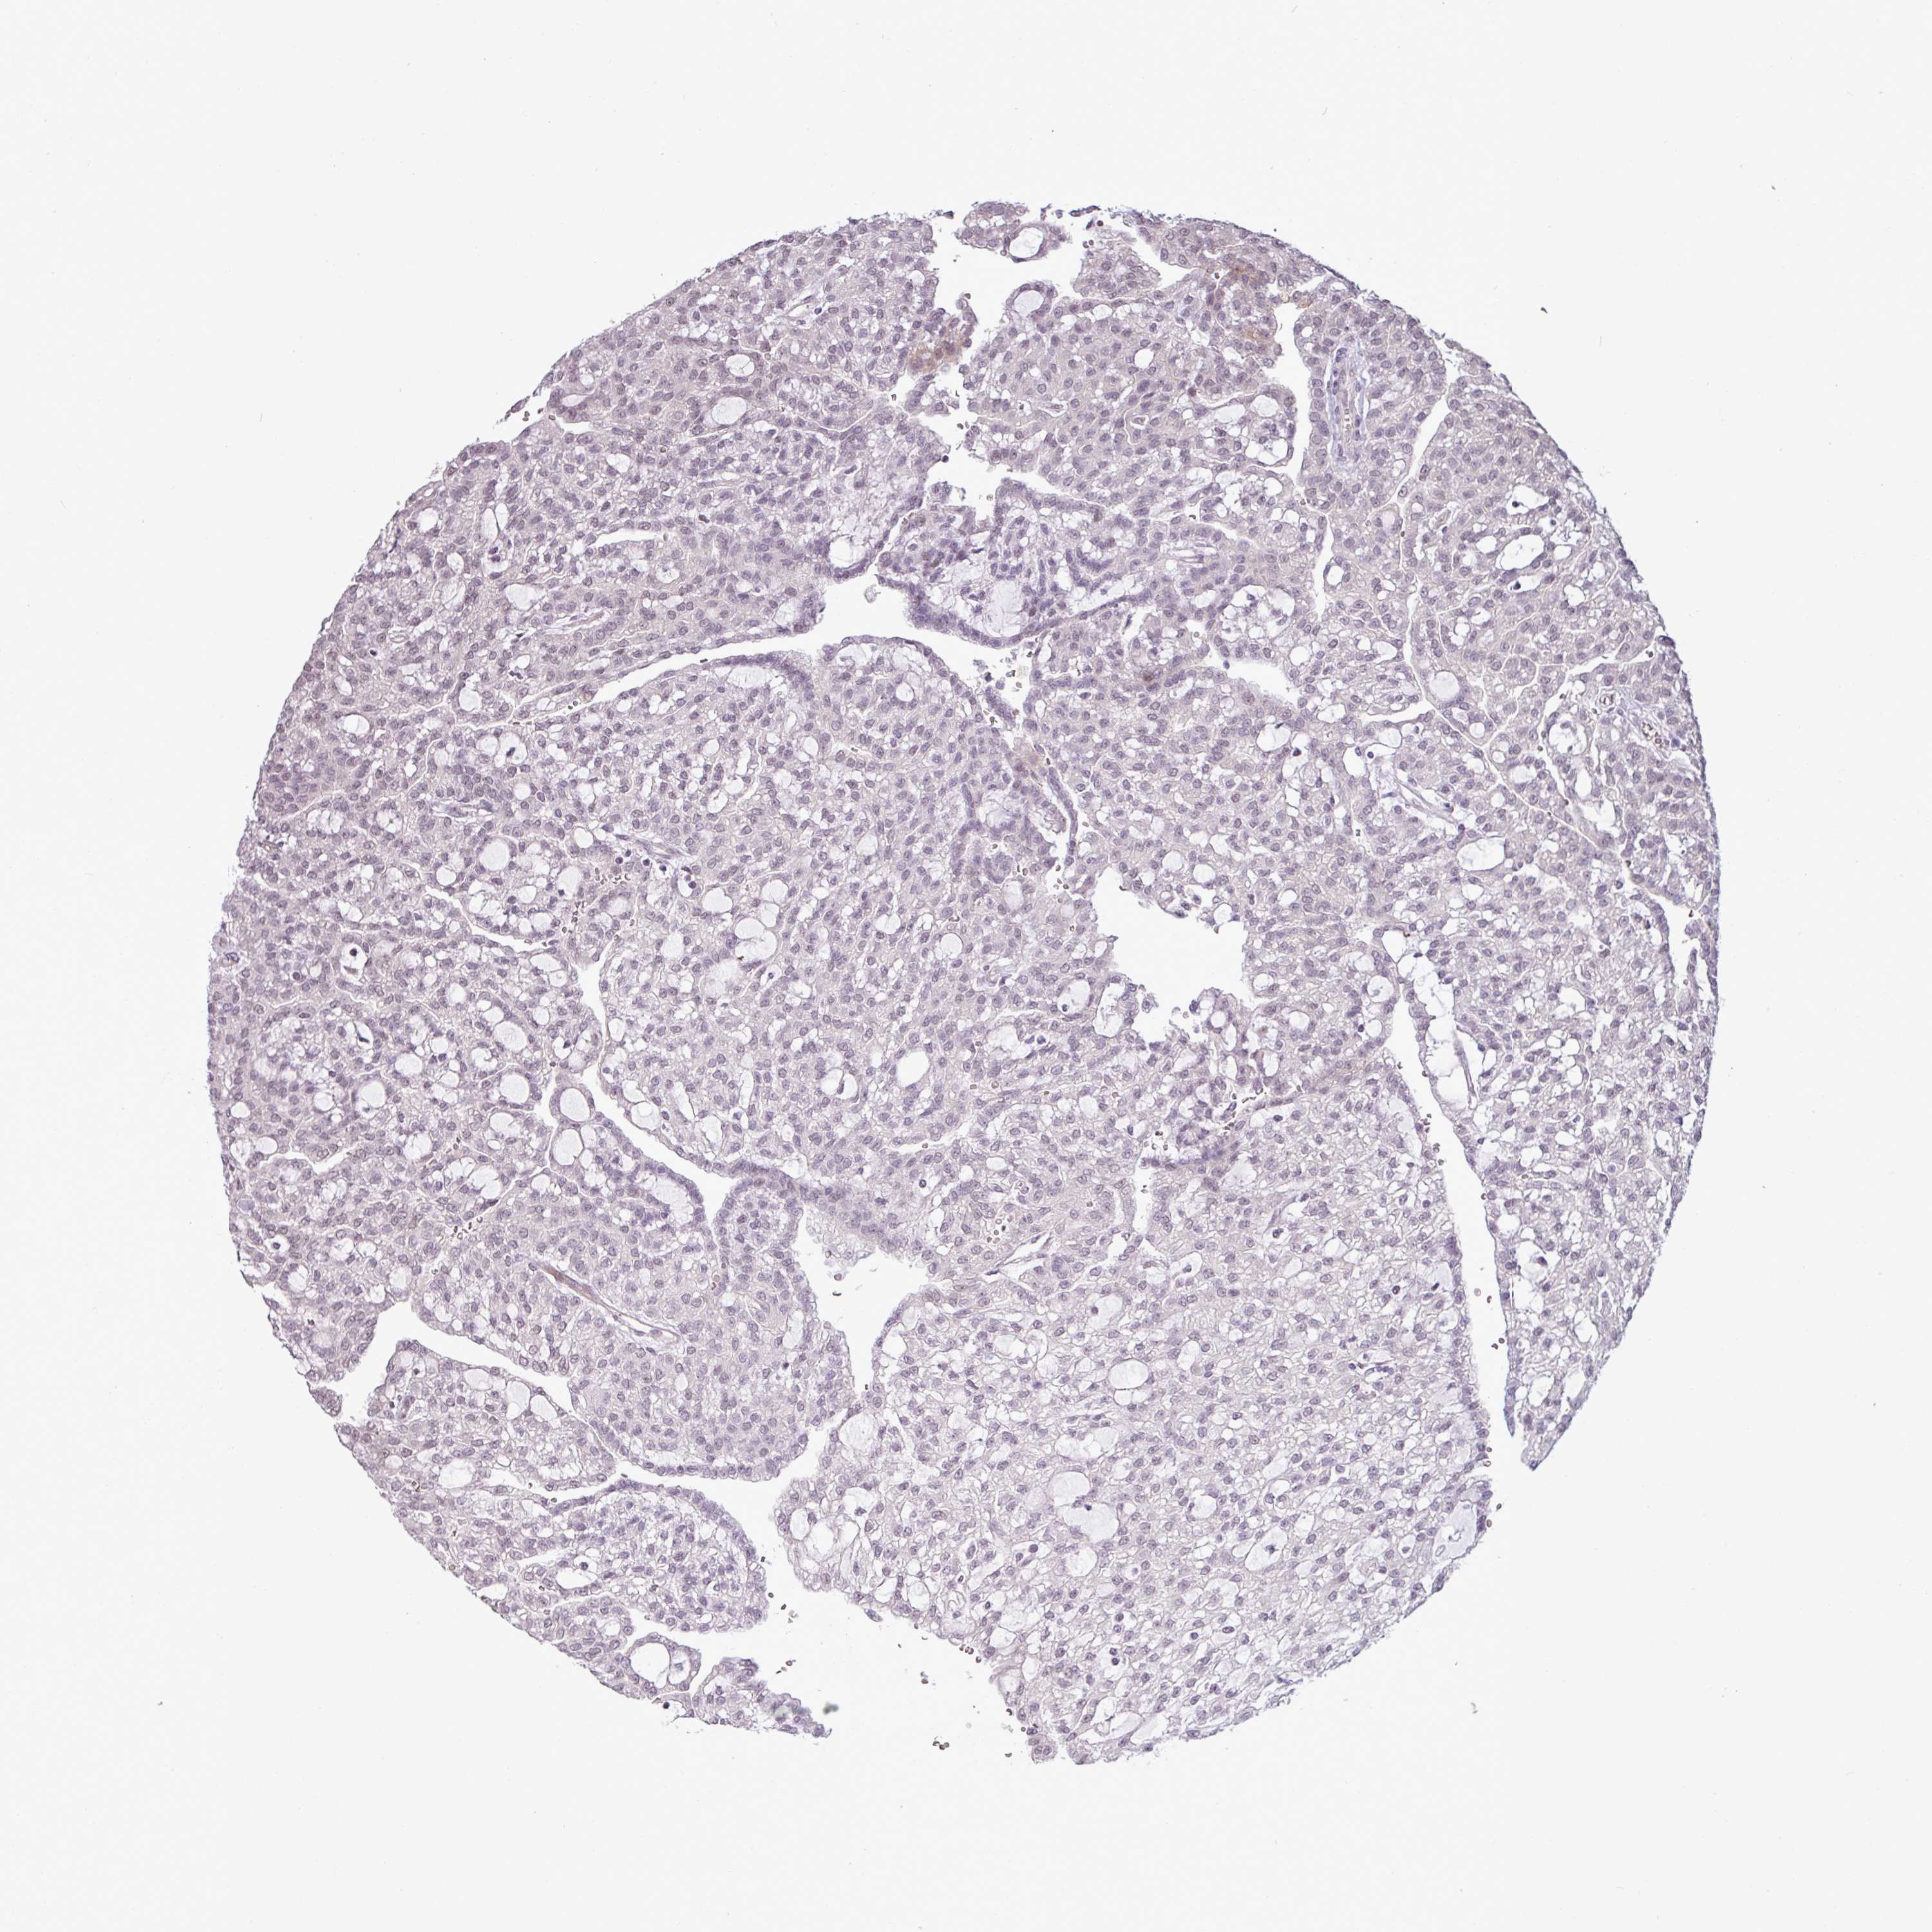

CANCER RENAL CANCER Show tissue menu

KICH TCGA KIRC TCGA KIRC VALIDATION KIRP TCGA PROTEIN RCC CPTAC PROTEIN EXPRESSION